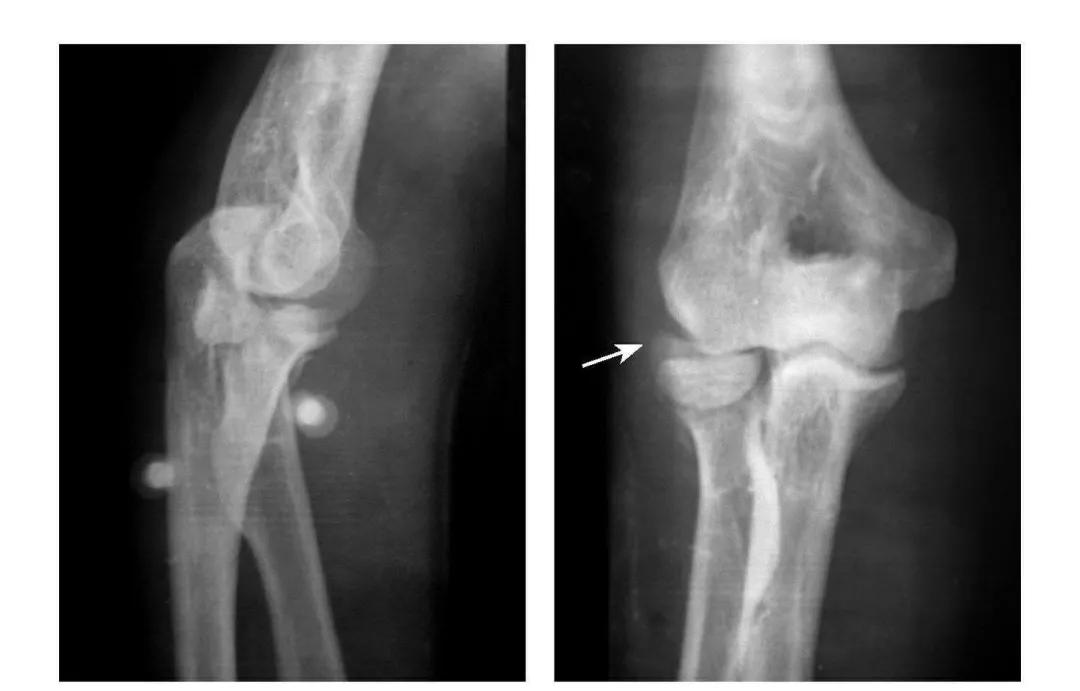

2

肘过伸应力综合征

例:①鹰嘴突劈裂骨折;②肱骨小头及滑车基底部骨折且整体前移;③肱骨内上髁Ⅱ型骨折;④肱骨外髁Ⅱ型骨折。